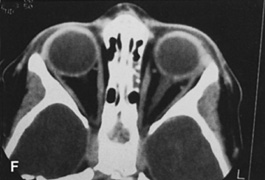

Fig. 25. A,B. Coronal (A) and axial (B) CT scans demonstrating well-encapsulated mass posteriorly in the superonasal orbit. An excellent alternative to transcranial orbitotomy for this lesion is an anterior approach via a vertical-lid splitting incision.